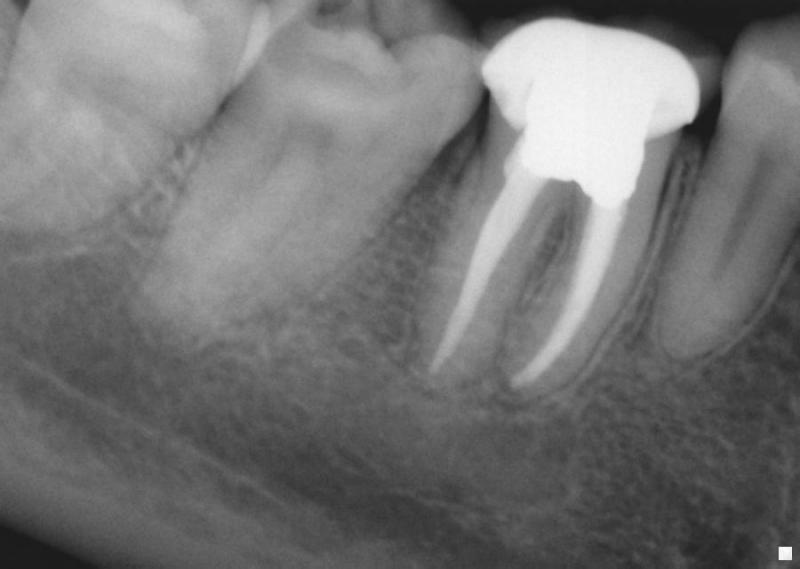

From www.researchgate.net

Endodontic treatment 2.2. (a) Periapical Xray endodontic overfilling Endo X Ray Tips Dental radiography allows for the identification of pathologic. Radiographs aid in making an endodontic diagnosis; However, clinical tests and examination, and the patient's medical and dental history must be considered. Getting working length radiographs during an endodontic. Endodontics aims to prevent or eliminate apical periodontitis. Basic tips for root canal xrays. Interpreting the information from a radiograph is notoriously subjective;. Endo X Ray Tips.